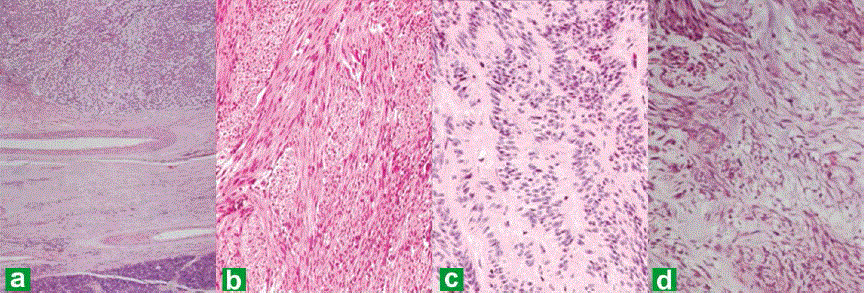

| Figure 3. Photomicrographs from the tumor in the pancreas showing pancreatic tissue at the periphery and the cellular lesion (40x) (a.). The tumorshowed predominantly fusiform spindle shaped cells in intersecting fascicles resembling a smooth muscle tumor (b.), with foci of nuclear pallisading reminiscent of a neural tumor (c.), and myxoid areas (d.) (H&E, 100x). |